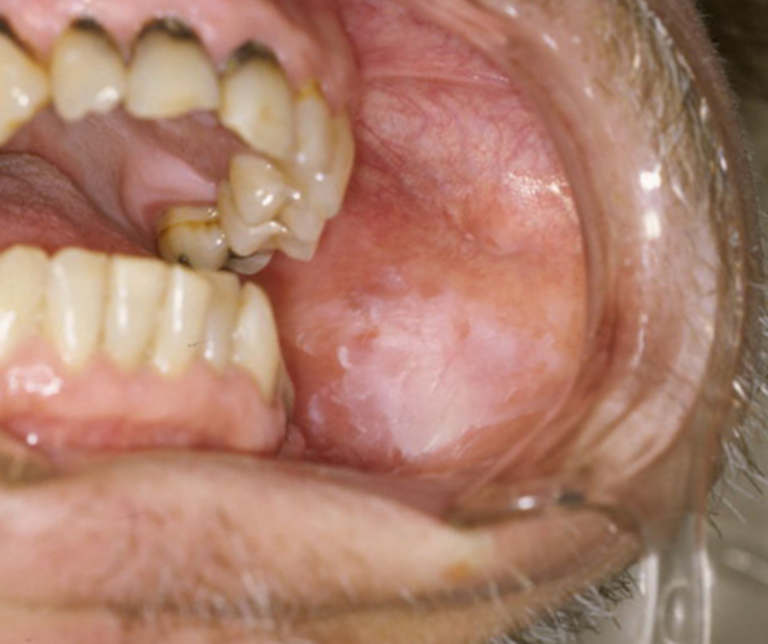

白板症(はくばんしょう)

舌の脇や歯茎、頬の粘膜が白く変化し、こすっても取れない状態です。

口腔がんへ移行する確率が比較的高い「前がん病変」とされており、精密な経過観察、あるいは専門機関での組織検査が必須です。